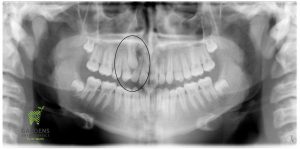

Initial and Final Panoramic X-rays showing an impacted canine (upper right) erupted in place